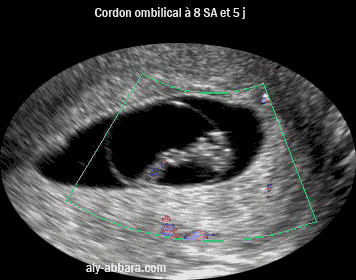

Image échographique montrant l'aspect du cordon ombilical et la circulation sanguine funiculaire chez un embryon de 8 SA et 5 jours ± 2 jours ( 6 semaine de gestation et 5 jours ± 2 jours)

• On remarque sur cette image que le cordon ombilical s'insère d'un côté sur le tronc de l'embryon, et de l'autre côté, sur le chorion à l'endroit où l'amnios reste adhérant au trophoblaste, c'est-à-dire à l'endroit où il s'est formé dans des stades embryonnaires plus précoces (2 et 3e semaines de gestation) le pilier de fixation de l'embryon

• On remarque aussi sur cette image, que l'embryon et le cordon ombilical flottent dans le sac amniotique limité par l'amnios. Le sac amniotique occupe, avec le cœlome externe, la cavité choriale (ou le sphère chorial) qui est entourée par le chorion fixé à l'endomètre